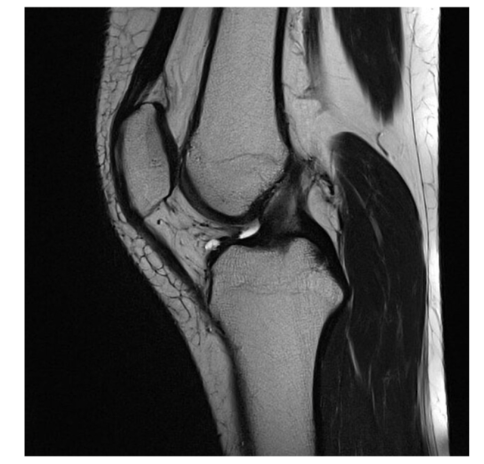

Sequence + pathology?

• 1st = PD: intermediate signal from muscle and fat is bright, image quality is much better

• 2nd = PD FS: fat has been supressed appearing much darker

• Path = complete ACL tear: in a normal knee you would see a black band which is the acl sitting

across the anterior aspect of the tibia and extending to the posterior aspect on the femur. This is not present at all hence, a tear.